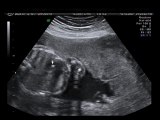

Echogenic intracardiac focus